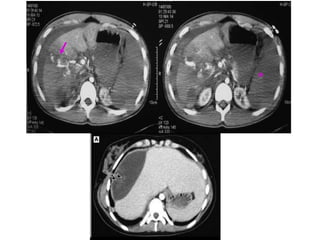

TRAUMA HEPÁTICO

• Segundo órgão mais acometido no trauma

fechado de abdome. E, segundo o ATLS, o

terceiro mais identificado em lesões

abdominais penetrantes, principalmente

devido à extensão de seu parênquima.

TRATAMENTO CONSERVADOR

Estáveis hemodinamicamente sem sinais de

peritonite  Repouso absoluto por 5 dias (as

primeiras 48h em UTI)/ Acompanhamento de sinais

vitais/ Medidas de Ht seriadas (Se queda, solicita-se

nova TC de abdome)

Extravasamento de contraste na fase arterial da TC

Tipo 1  Laparotomia

Tipo 2  Angiografia + Embolização

Tipo 3  Angiografia